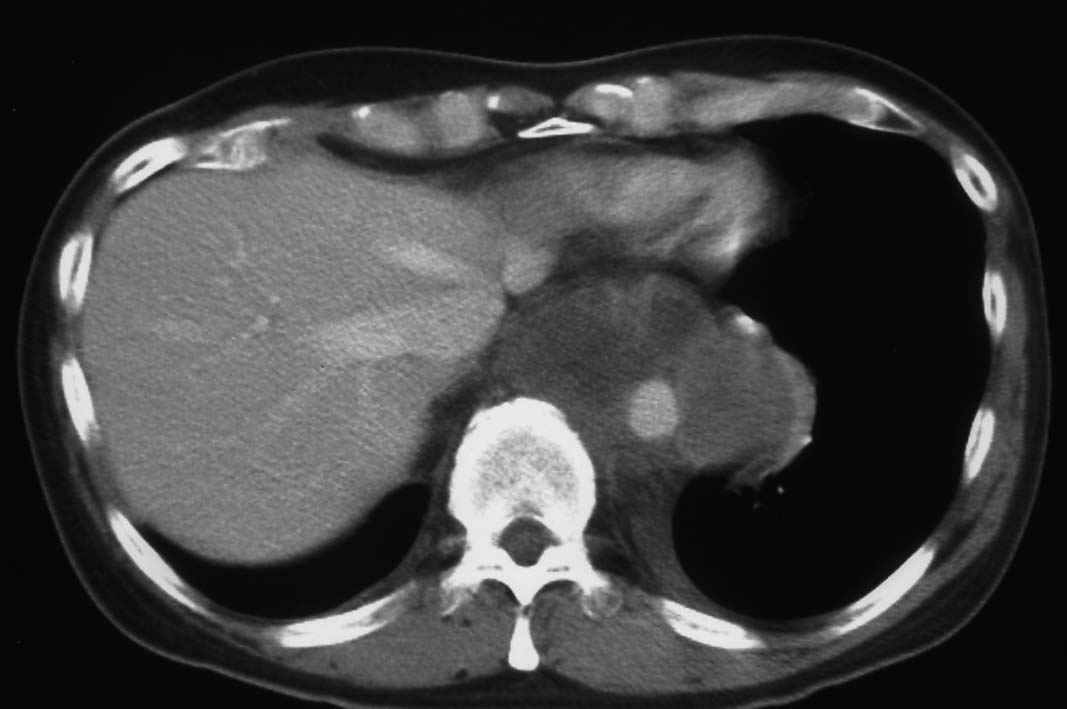

胸腔鏡下ブラ切除術5ヵ月後, 縦隔腫瘤で再発. 他院で腫瘍切除+右肺上葉切除を施行. 肉眼的には腫瘍は完全に切除できた.

病理診断は, 非典型的所見ながらmalignant solitary fibrous tumorとされた.(剖検時点ではSMARCA4-DTSの疾患概念はなく, 知見も得られていなかった.)

初診から11ヵ月, 胸部つかえ感出現. CTで気管分岐部から横隔膜食道裂孔を通り, 腹腔内へ進展, 食道および大動脈を囲繞する巨大な腫瘍が再発した. 他院での抗がん剤感受性テストの結果より, CDDP+5FUによる化学療法がおこなわれたが効果乏しく全身状態悪化. 呼吸不全が進行し初診より約1年の経過で永眠された.